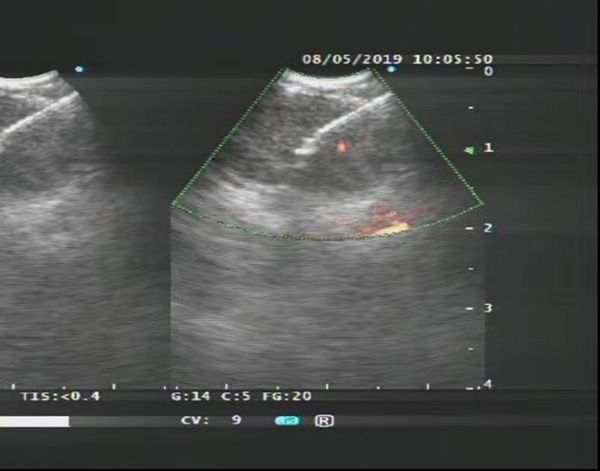

一 概述消化道出血是临床常见症候群,可由多种疾病所致。消化道是指… [更多]